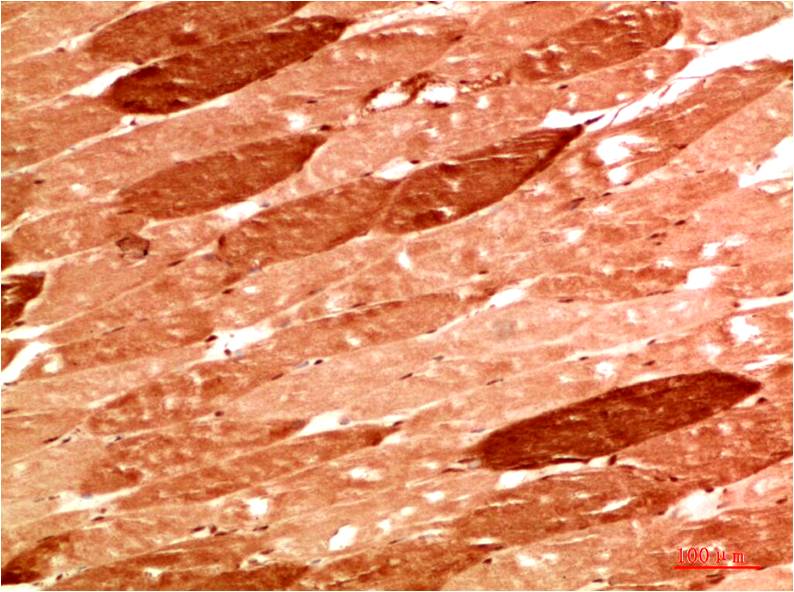

IkB α Rabbit Polyclonal Antibody

Applications :WB, IHC

| Recommended dilutions: | WB 1:500-2,000 IHC 1:50-300 |